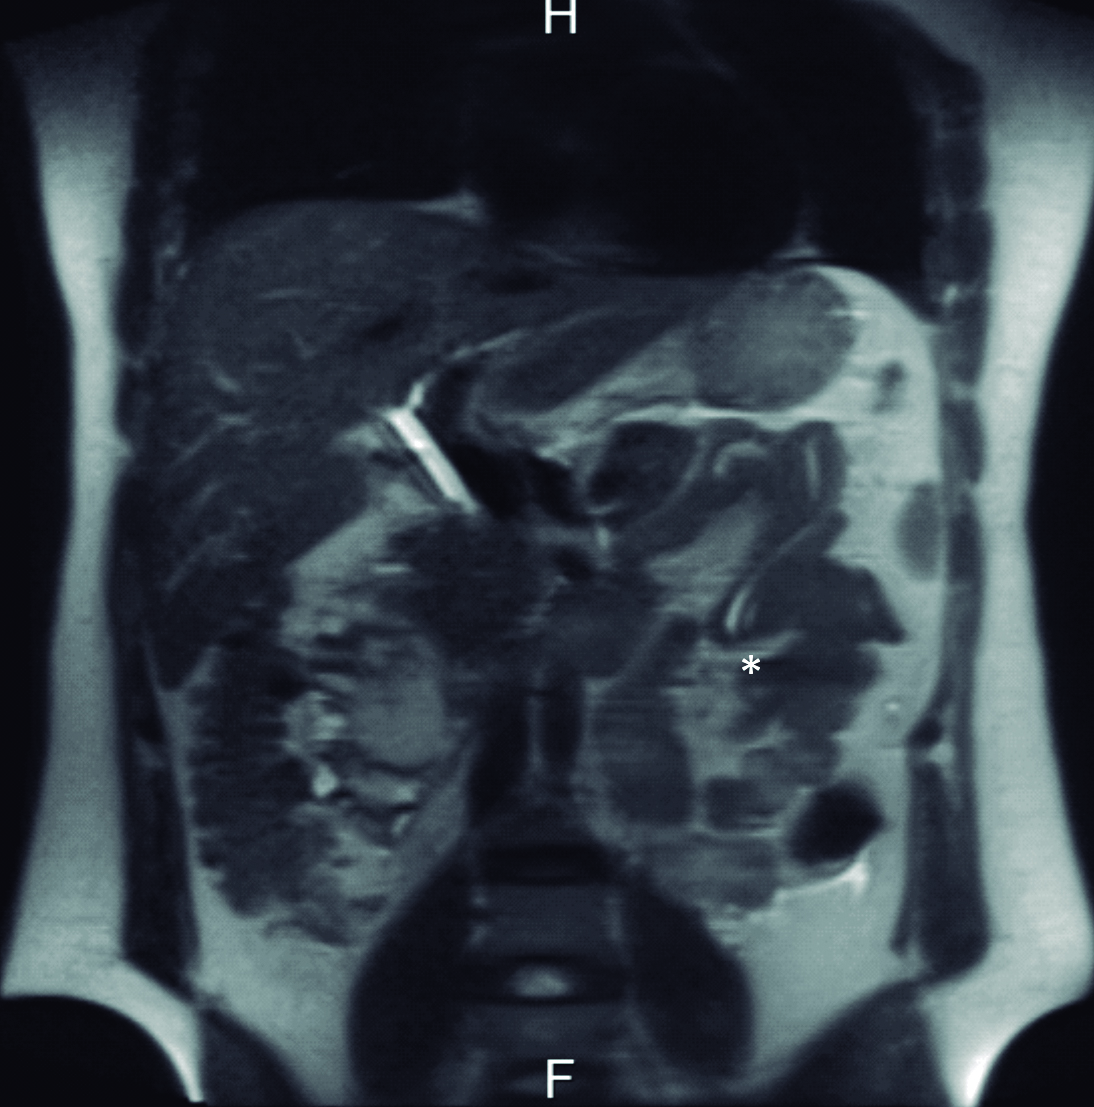

Se interroga a la paciente y refiere haber sido estudiada previamente con una colangiografía por resonancia magnética tres meses previo a la consulta en otro centro hospitalario. En ese momento la vía biliar principal no estaba ocupada. Retrospectivamente se identificaron los parásitos en el tubo digestivo proximal (Fig. 4 y 5).

Figura 4. Resonancia Magnética

a y b) Imágenes en plano coronal potenciadas en T2 sin saturación grasa. A nivel de asas yeyunales proximales se identifican los parásitos

como imágenes lineales ligeramente hiperintensas con un área central hipointensa (*).

La resonancia magnética es una excelente modalidad no invasiva para diagnosticar la presencia de parásitos en la vía biliar. En imágenes ponderadas en T1, los gusanos se ven como estructuras tubulares lineales ligeramente hiperintensas con un área central hipointensa y en la colangiografía por resonancia se visualizan como defectos lineales de relleno hipointensos en el tracto biliar. (4, 9, 10)